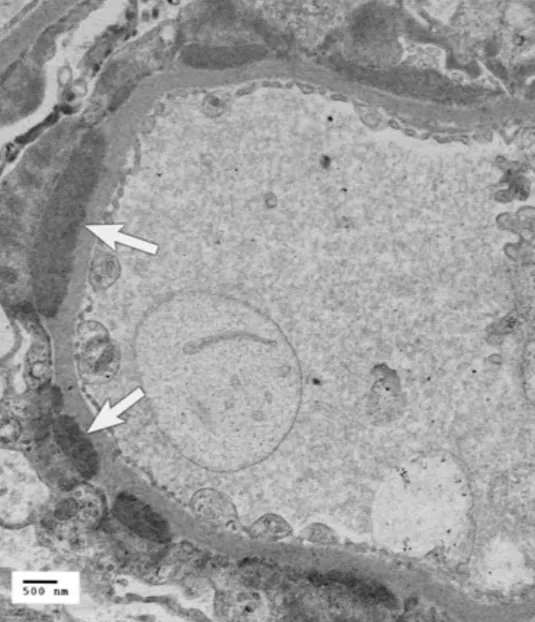

🔺如何確診免疫絲球體腎病

🔹腎臟生檢下在顯微鏡下看到絲球體受到傷害

🔹電子顯微鏡下:看到免疫複合體的沉積

🔹免疫螢光顯微鏡:看到免疫複合體的沉積

穿透式電子顯微鏡